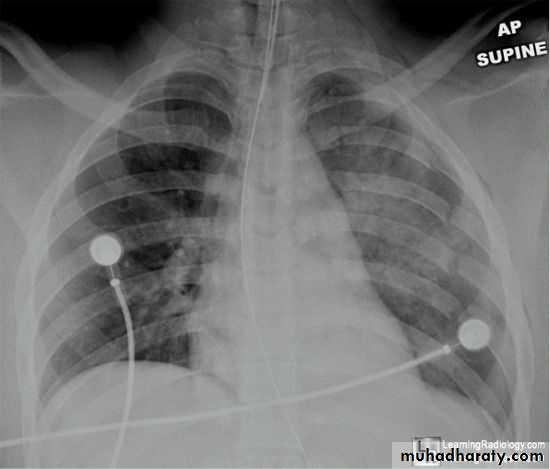

Severe dyspnea with shock